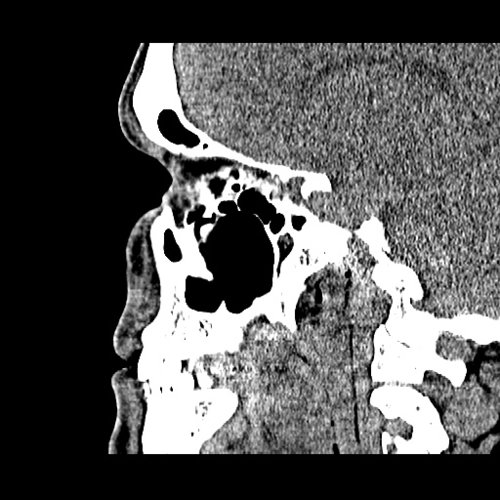

From www.embodi3d.com

Chronic sinusitis Dental, Orthodontic, Maxillofacial CTs Orthodontic Sinusitis The maxillary sinus is the paranasal sinus that impacts most on the work of the dentist as they will often be required to make a. Odontogenic maxillary sinusitis (oms) is a subtype of maxillary sinusitis (ms). It is actually inflammation of the maxillary sinus. Odontogenic sinusitis (ods) can present a therapeutic dilemma because multiple treatment strategies have been reported. A. Orthodontic Sinusitis.